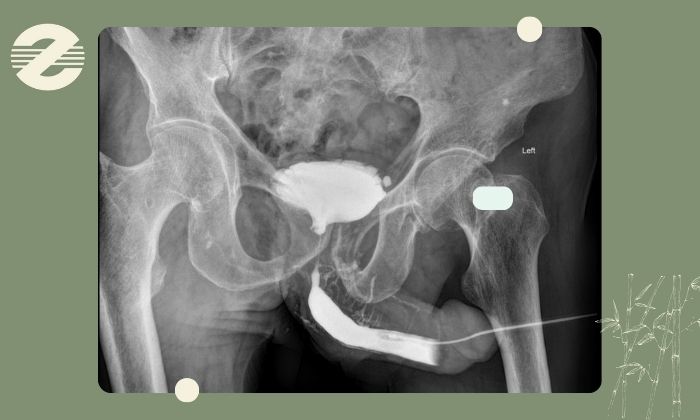

این تست بهدلیل دقت بالا و توانایی نشاندادن جزئیات ریز مجرا، یکی از بهترین انتخابها برای تشخیص مشکلات مجرای ادراری محسوب میشود.